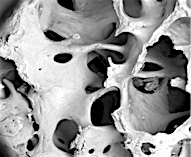

По внешнему виду представляет собой пористый губчатый блок номинального размера.

2. Поверхность и структура материала для изготовления биоимплантатов